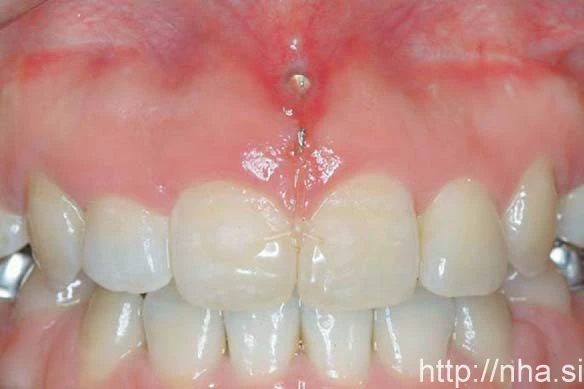

Khi sử dụng minivis tại đầu xa cung răng với mục đích neo chặn, sẽ gây ra khó kiểm soát sự trồi các răng trước hàm trên, hiện tượng này có thể xảy ra trong quá trình kéo khối 6 răng phía trước do hiệu ứng cuộn của dây cung. Trong trường hợp cần đánh lún các răng phía trước, có thể dùng phương pháp cắm minivis tại xương vỏ mặt ngoài phía dưới gai mũi trước và tác dụng lực đánh lún thông qua chun chuỗi. Chun chuỗi được mắc vào các button và dán vào mặt ngoài hai răng cửa giữa (Hình 5).

minivis cắm ở mặt trước xương hàm trên của một bệnh nhân niềng răng mặt trong.

Hình 5 Minivis cắm ở mặt trước xương hàm trên của một bệnh nhân niềng răng mặt trong. Buộc chun chỉ từ minivis tới các button composite trong suốt được dán vào mặt ngoài các răng cửa giữa.